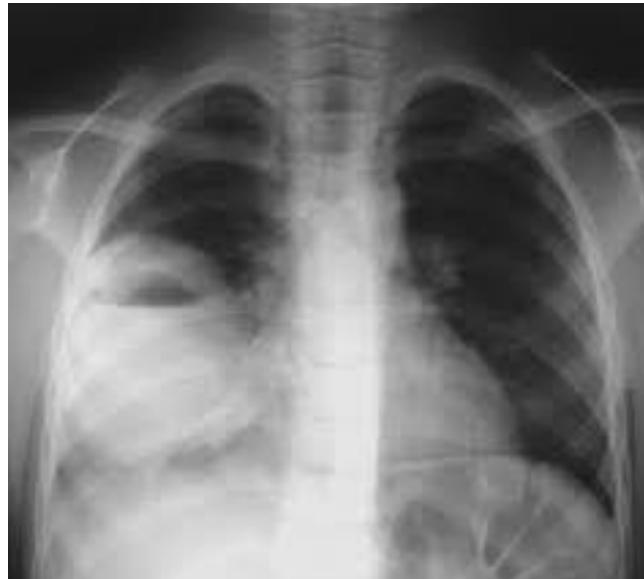

Pneumothorax

- Diagnosis: Right-sided Pneumothorax.

- Tension Pneumothorax (Clinical Diagnosis):

- Tracheal deviation to the opposite side.

- Hyperresonance on percussion.

- Congested neck veins, hemodynamic instability.

- Treatment of Tension Pneumothorax: Urgent needle decompression followed by chest tube insertion.